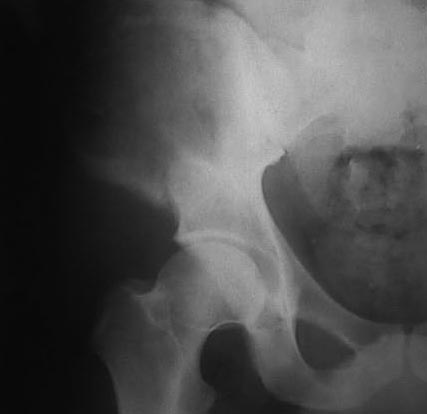

Могу пока выложить еще снимки и показать хронологию данного процесса и его прогрессирование, первый снимок был 2011 года. Вот этот 2009

И 2010 год